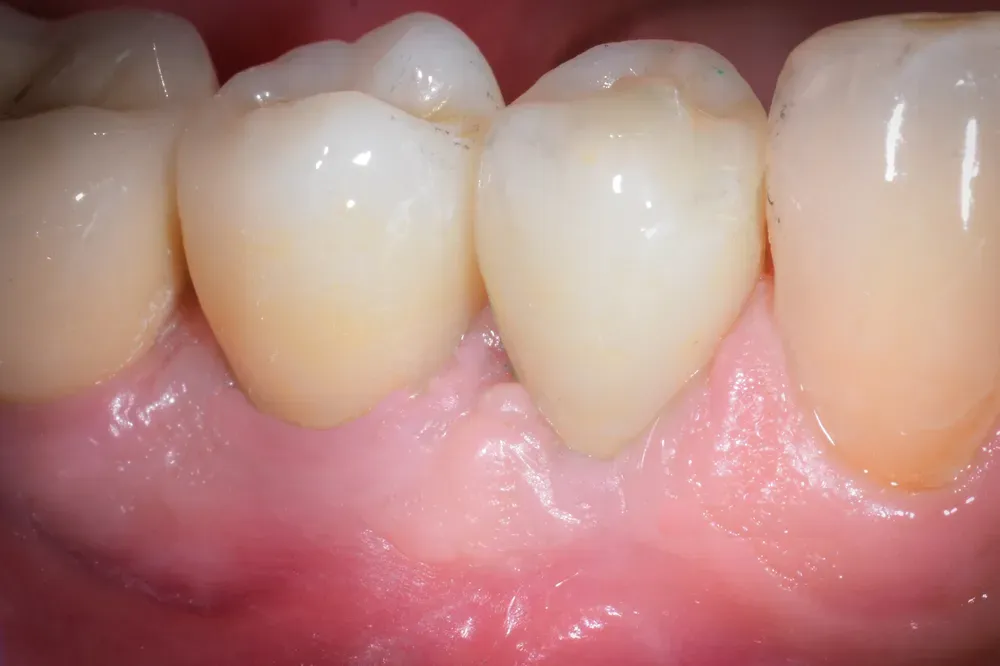

L’immagine sottostante mostra i tessuti perimplantari prima della scansione finale (con scanner intraorale) per realizzare le corone in ceramica.

I volumi dei tessuti sono ben conservati anche buccalmente al primo premolare, dove l’osso alveolare sull’aspetto buccale era totalmente assente al momento dell’estrazione e del posizionamento dell’impianto.

I contorni delle corone in ceramica finali sono naturali e le dimensioni della mucosa cheratinizzata sono preservate in modo ottimale, a beneficio della salute a lungo termine degli impianti.

Tessuti peri-implantari dopo 2 mesi di guarigione prima della scansione finale per le corone in ceramica.